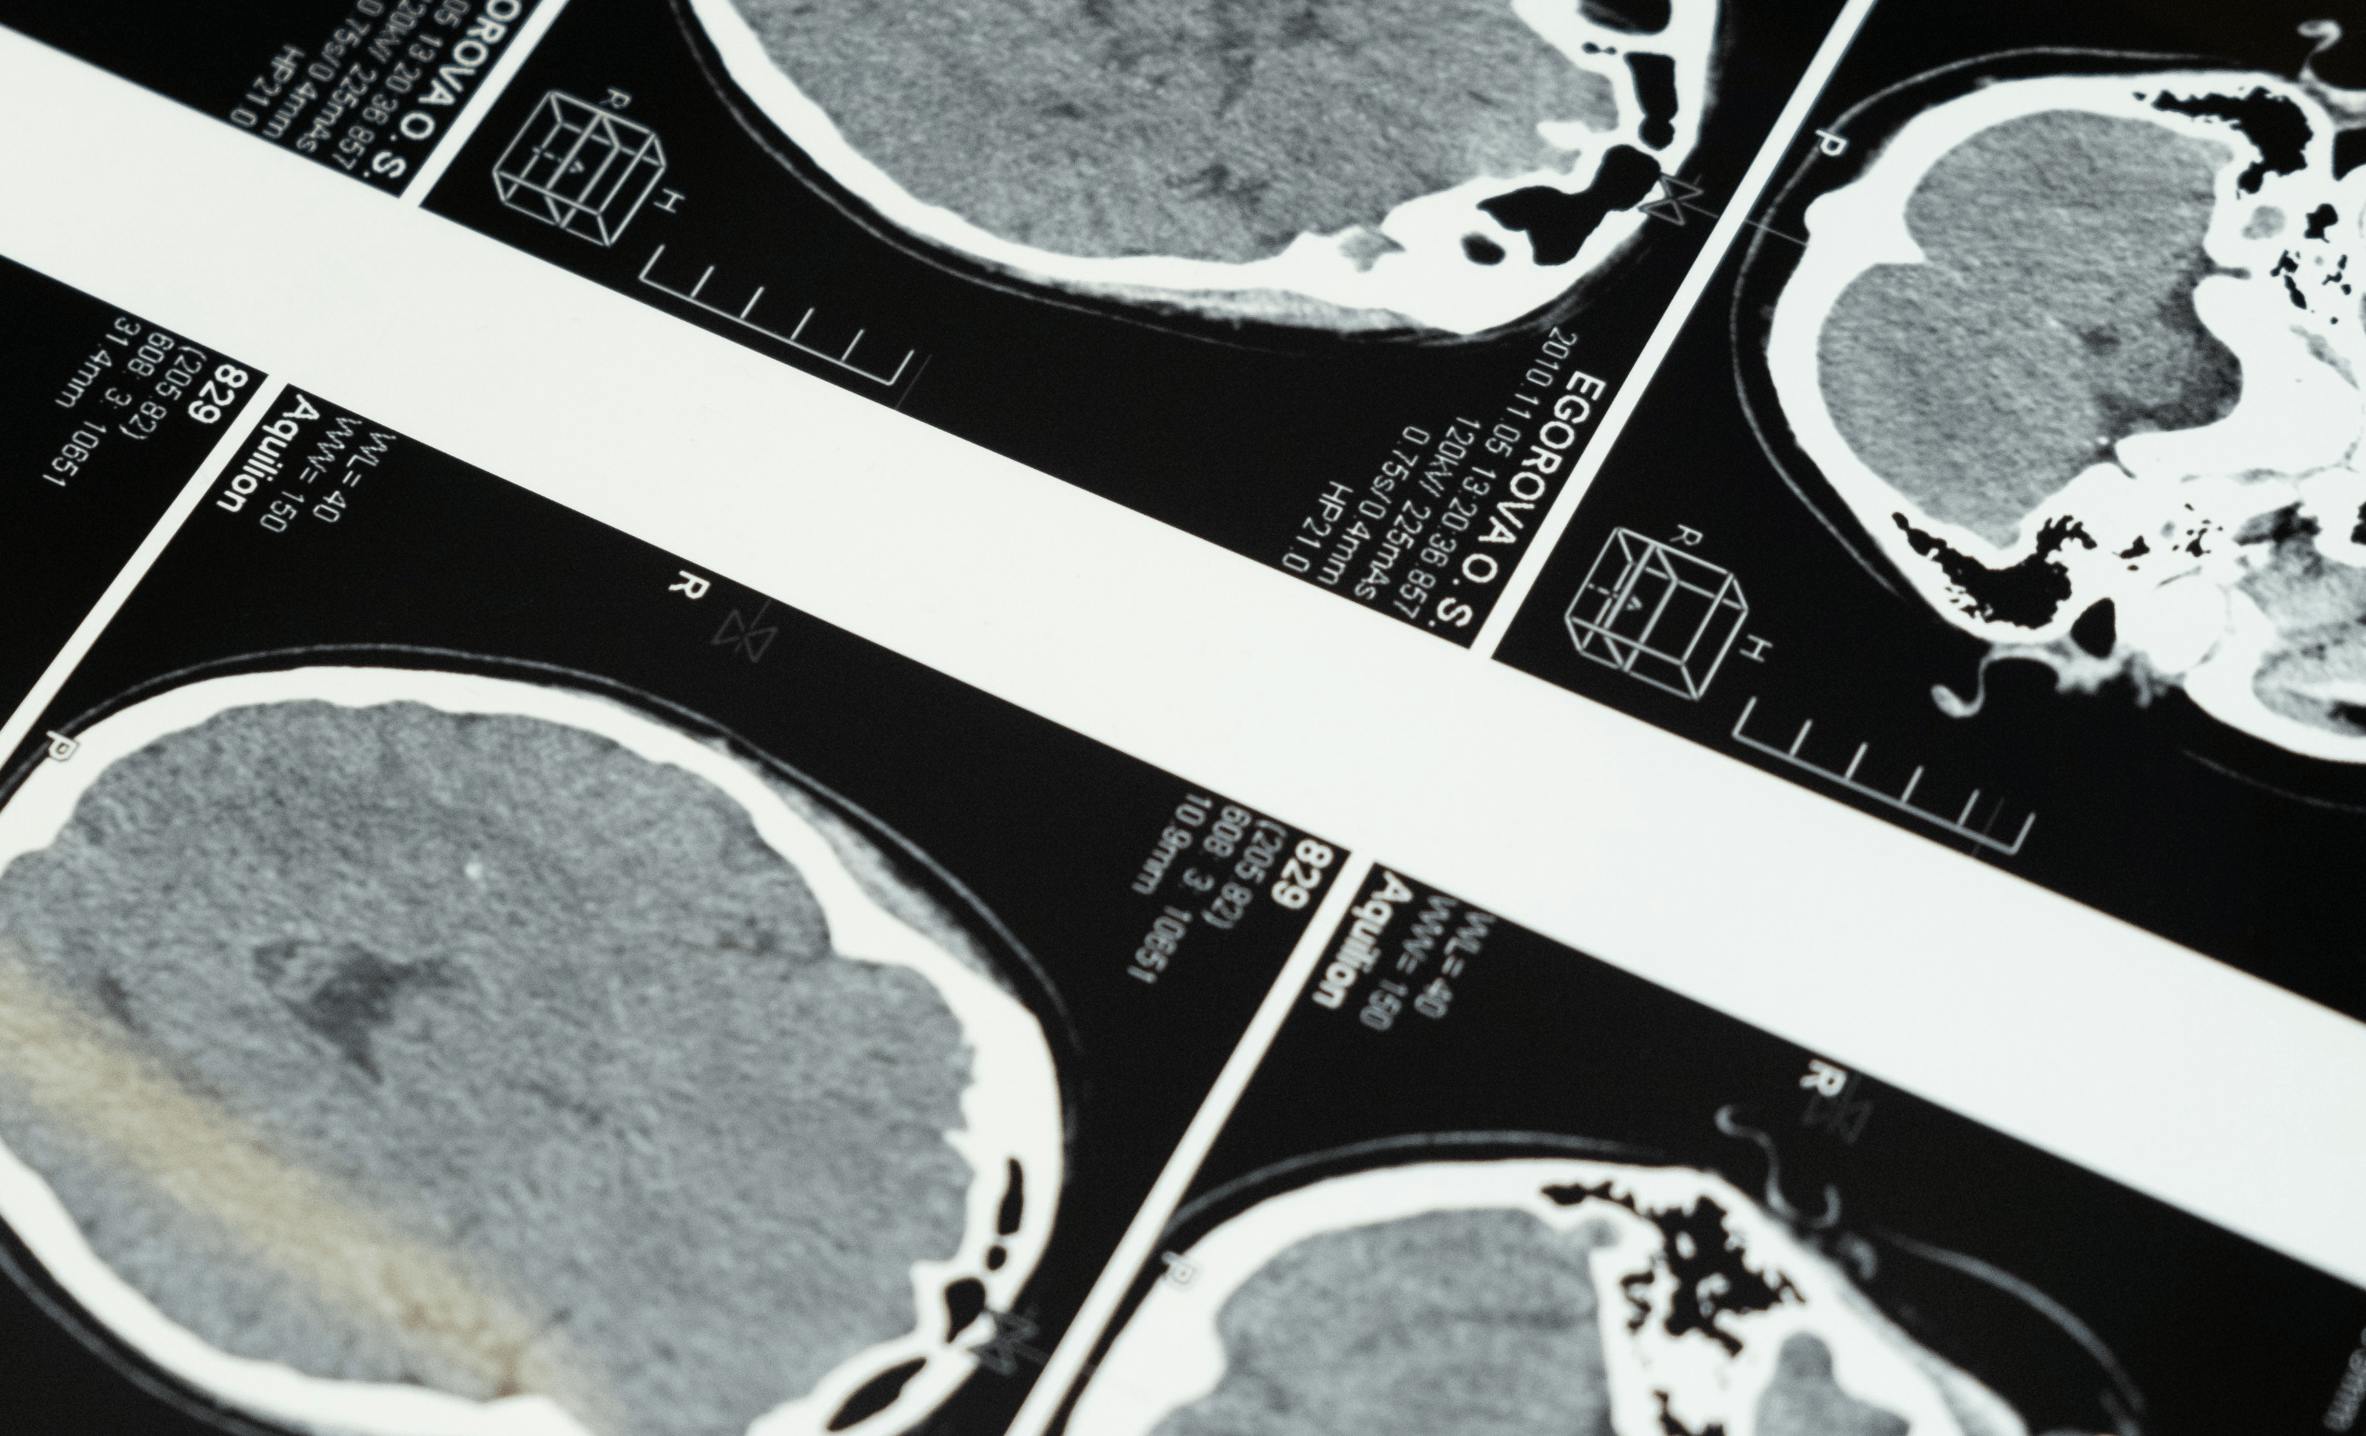

Reducing MRI and CT Annotation Time by 70% for Rapid AI

RapidAI develops AI that helps medical professionals identify and provide treatment for stroke victims. The company works with multiple annotators to label vast datasets of medical imaging. When managing the annotation and review process for large projects became unwieldy, the company turned to Encord’s platform for a seamless, centralized annotation experience.

When diagnosing stroke patients, doctors use perfusion and diffusion imaging. However, perfusion imaging is a complicated process: obtaining the results is time-consuming, and perfusion scans provide a lot of information that doctors must compile and analyze quickly. If doctors had more immediate access to a summary image that provided meaningful information, they could quickly identify patients who would benefit from care, extending the time frame for treatment.

In 2012, Albers and Bammer founded RapidAI. Building on the technology they’d developed at Stanford University; the company provides brain imaging software tools designed to help doctors extract greater meaning from patient data. By creating high-quality images from diffusion and perfusion data, RapidAI’s technology assists neurovascular and vascular teams in making faster, more accurate diagnoses and treatment decisions.

To train a model, RapidAI’s machine learning teams need thousands of labeled CT, CTA, MR, and MRA images. Each training project consists of about 500 cases, with between 30 and 200 CT image slices per case. If the case contains CTA scans, that number is closer to 1000 slices.